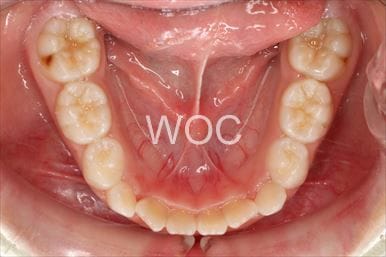

叢生

治療前1

治療前2

治療前3

治療前4

治療前5

- 年齢:7歳9ヶ月

- 主訴:スペースがない、デコボコしている

- 診断名:叢生、上顎前突、過蓋咬合

- 装置:可撤式拡大装置、機能的矯正装置

- 期間:4年1ヶ月 ※

- 費用:基本矯正料金:380,000円